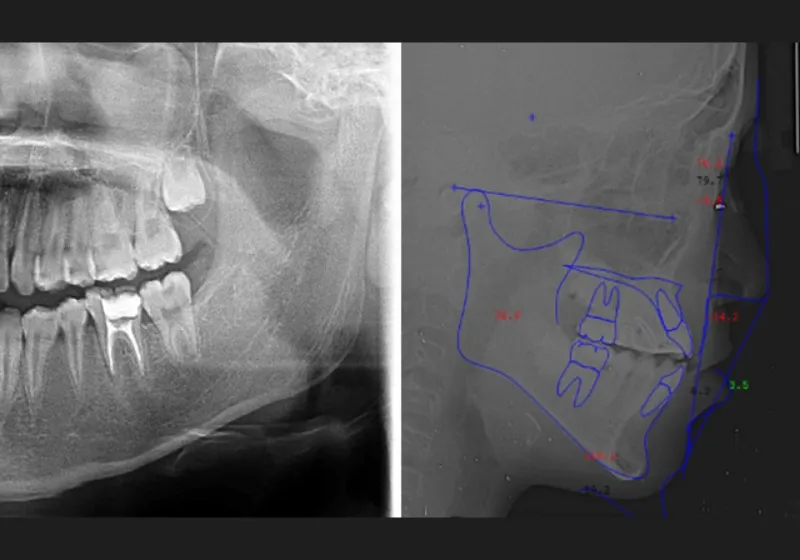

精密検査

診断に必要な情報を収集するため、歯型の採取や顔や口腔内の写真撮影、パノラマレントゲン撮影、頭部X線規格写真撮影などの精密検査を行ないます。また、お口の健康状態を知るために虫歯や歯周病の検査も実施します。